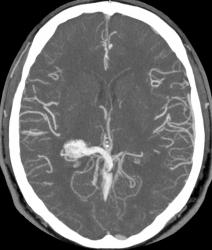

Предсталяю артериовенозную аневризму. Может кому-нибудь будет интересно.

Виден клубок неправильно развитых сосудов, питающихся от задней мозговой артерии и дренирующийся в прямой синус. Перифокальных изменений нет.

Черная стрелка - питащий сосуд - задняя мозговая артерия, зеленая - дренирующая вена к прямому синусу, красная - прямой синус.

Я чуть увеличил фрагменты изображений с "патологическим состоянием"

Очень наглядна видна сосудистая мальформация.

Питание идет из гипертрофированных задней мозговой и средней мозговой артерий (красные стрелки), дренирование в основном в верхний сагиттальный синус (синий кружок). Дренирующая вена - синие стрелки.